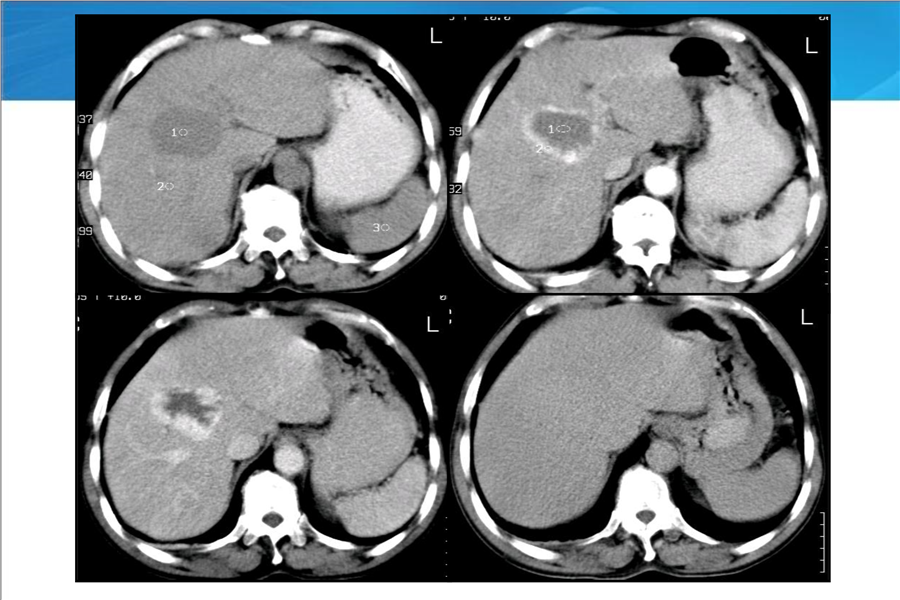

消化系统二